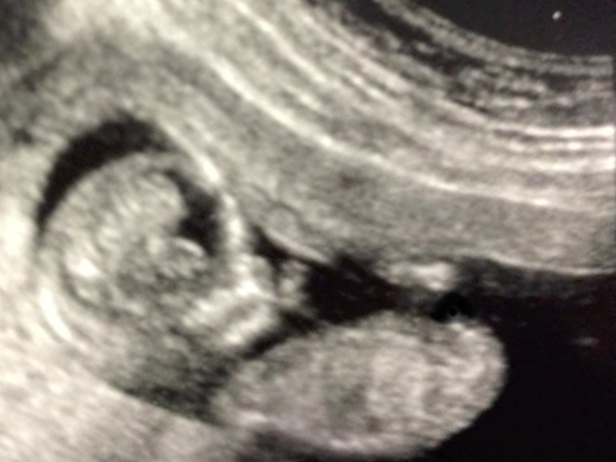

highlighted in green is your partial. Its because of the angle appearance i lean boy but without seeing the whole thing on a non curled up baby its anyones guess!Attachment 24111

Thanks! Yeah that was what I assumed was the nub but because of the curled spine and legs up by his/her head I couldn't work out what the angle was, or if it was the nub at all! I was wondering if the little bobble to the left of the green line was the nub too, but I just don't know!

yeah its possibly part of it but just too much static and everything in the way